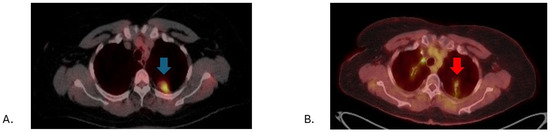

- Paez-Carpio, A.; Gomez, F.M.; Isus Olive, G.; Paredes, P.; Baetens, T.; Carrero, E.; Sánchez, M.; Vollmer, I. Image-guided percutaneous ablation for the treatment of lung malignancies: Current state of the art. Insights Imaging 2021, 12, 57. [Google Scholar] [CrossRef] [PubMed]

- Smith, S.L.; Jennings, P.E. Lung radiofrequency and microwave ablation: A review of indications, techniques and post-procedural imaging appearances. Br. J. Radiol. 2015, 88, 20140598. [Google Scholar] [CrossRef]

- Mansur, A.; Garg, T.; Shrigiriwar, A.; Etezadi, V.; Georgiades, C.; Habibollahi, P.; Huber, T.C.; Camacho, J.C.; Nour, S.G.; Sag, A.A.; et al. Image-Guided Percutaneous Ablation for Primary and Metastatic Tumors. Diagnostics 2022, 12, 1300. [Google Scholar] [CrossRef]